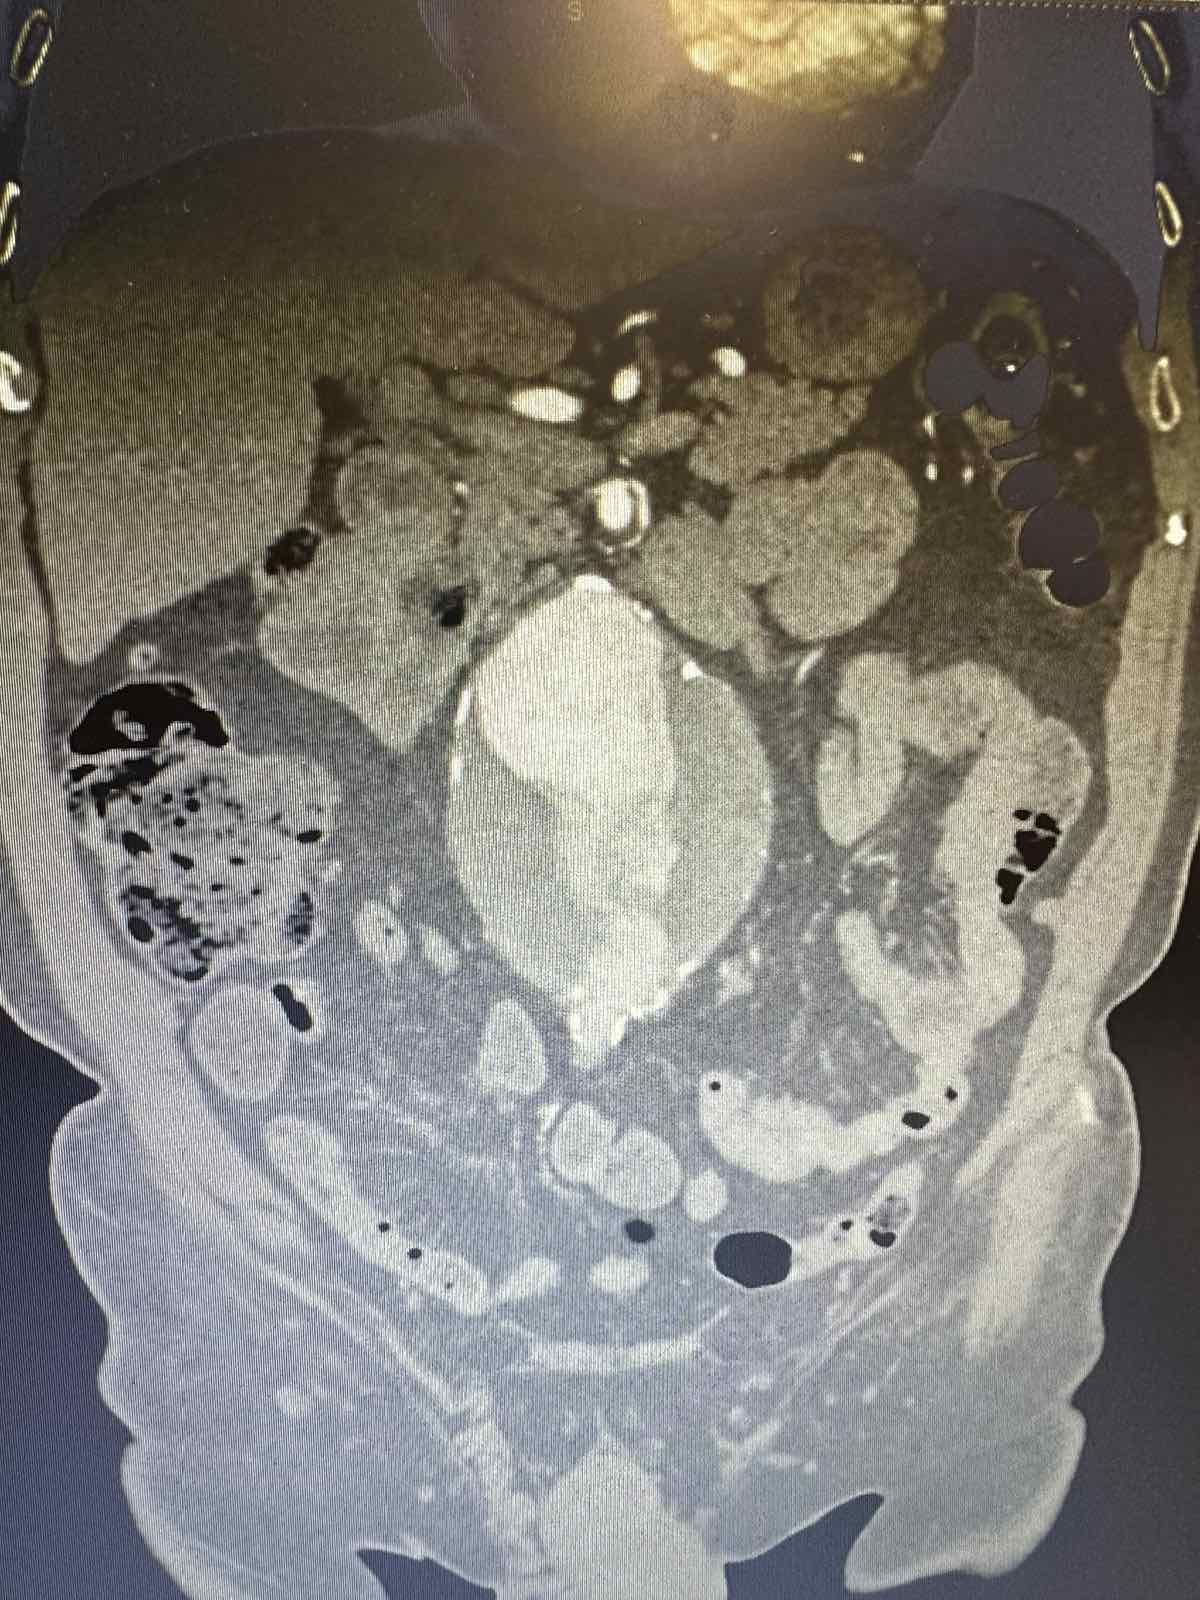

Η διάγνωση του ανευρύσματος κοιλιακής αορτής γίνεται με triplex κοιλιακής αορτής ή αξονική τομογραφία κοιλίας. Κάθε άνθρωπος (στο πλείστο των περιπτώσεων άνδρας) που υπερβαίνει το 60ο έτος της ηλικίας του πρέπει να ελέγχεται με triplex κοιλιακής αορτής (εάν έχει 1ου βαθμού συγγενή με ανεύρυσμα κοιλιακής αορτής η εξέταση πρέπει να γίνει μετά το 50ο έτος). Σε ασθενείς που χρειάζονται αποκατάσταση του ανευρύσματος κοιλιακής αορτής η πιο λεπτομερή προεγχειρητική εξέταση είναι η αξονική αγγειογραφία κοιλιακής αορτής και λαγονίων. Σε ασθενείς που δεν μπορούν να υποβληθούν σε αξονική αγγειογραφία διενεργείται μαγνητική αγγειογραφία κοιλιακής αορτής και λαγονίων.